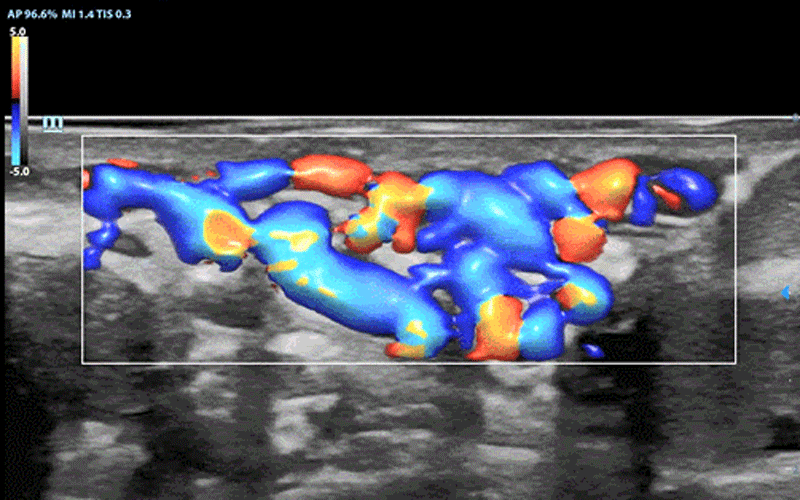

Moreover, the Glazing Flow indicates a breakthrough of color and power flow imaging which offers a brand new way to demonstrate the 2D color Doppler flow innovatively in a 3D visualization. It is able to provide intuitive and easy visualization of blood flow structures as well as boundary definition even for very tiny vessels which helps to achieve more clarity with less efforts. In this way, ultrasound users are able to acquire clear images within seconds even when they are fully zoomed in.

Varicocele with Glazing Flow